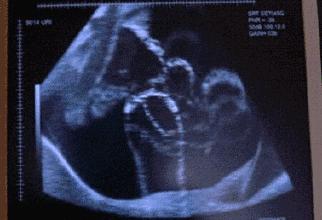

胎动,就是胎儿在子宫里的活动。最开始,因为宝宝还太小,所以妈妈们很难感受到。但是在18-20周之间,宝宝的手脚可以触碰到子宫壁,这时很多孕妈就可以感受到明显的胎动了。